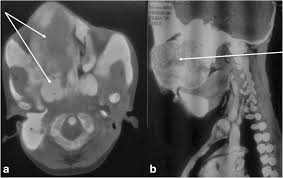

It is the only major dental journal that. Each chapter in GeneReviews is written by one or more experts on the specific condition or disease. OMIM174800 is a rare disorder characterized by skeletal lesions skin hyperpigmentation and hyper-functioning endocrinopathies 1 2It arises from post-zygotic gain-of-function mutations in the GNAS gene which encodes the α-subunit of the G s signalling protein These mutations disrupt the intrinsic GTPase.

Typically enchondroma is discovered on an X-ray scan. Oral Surgery Oral Medicine Oral Pathology and Oral Radiology Vol. It may predominantly affect the medullary portion andor cortex of bone. Each chapter in GeneReviews is written by one or more experts on the specific condition or disease. And The result of the test will directly impact the treatment being delivered to the member. OMIM174800 is a rare disorder characterized by skeletal lesions skin hyperpigmentation and hyper-functioning endocrinopathies 1 2It arises from post-zygotic gain-of-function mutations in the GNAS gene which encodes the α-subunit of the G s signalling protein These mutations disrupt the intrinsic GTPase. Cafè-au-lait skin pigmentations and endocrine dysfunction such as precocious puberty diabetes mellitus goiter and breast fibroadenomatosis 7 Radiographic features Typically seen as a well-circumscribed intramuscular mass. Oral Surgery Oral Medicine Oral Pathology Oral Radiology is required for all clinicians involved in the diagnosis and treatment of oral and maxillofacial disease. It is the only major dental journal that.